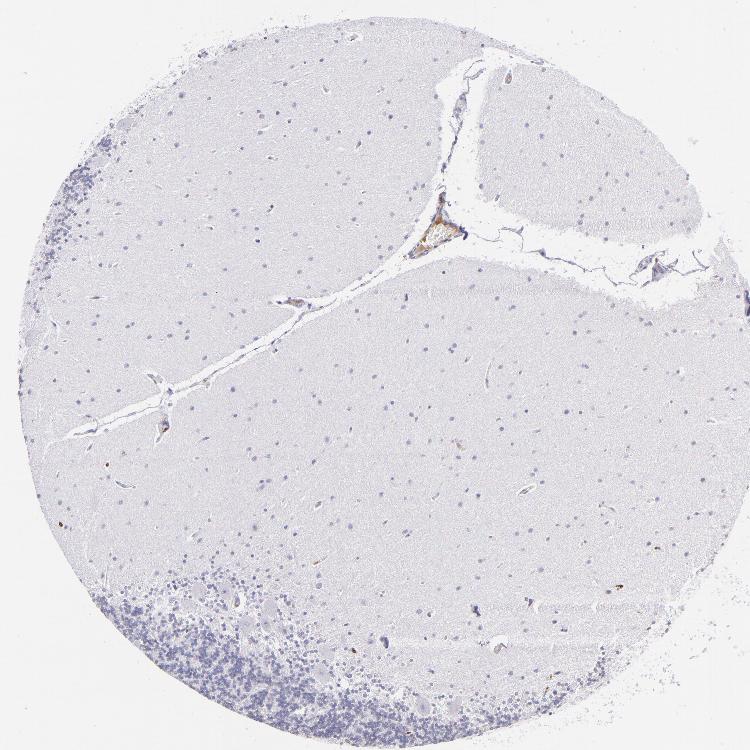

BRAIN CEREBELLUM Show tissue menu

CEREBELLUM - Expression summary

CEREBELLUM - Antibody stainingi

Antibody staining in the annotated cell types in the current human tissue is reported as not detected, low, medium, or high, based on conventional immunohistochemistry profiling in selected tissues. This score is based on the combination of the staining intensity and fraction of stained cells.

Each image is clickable and will lead to virtual microscopy that enables deeper exploration of all samples and also displays staining intensity scores, fraction scores and subcellular localization as well as patient and tissue information for each sample.

Antibody CAB002498

Purkinje cells Not detected

Cells in granular layer Not detected

Cells in molecular layer Not detected